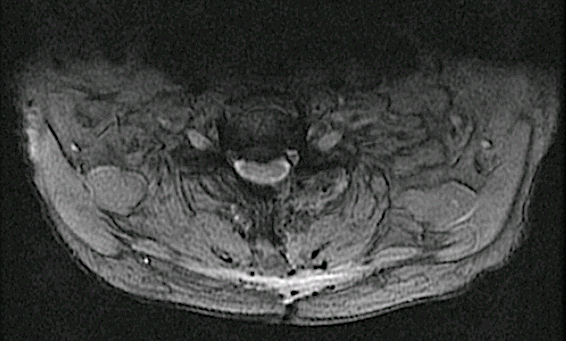

Rm 6 meses

Corte axial C7-Th1